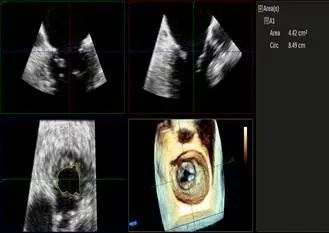

Qlab软件勾画估测瓣口面积约:4.42cm²

二尖瓣口平均跨瓣压差:5mmHg